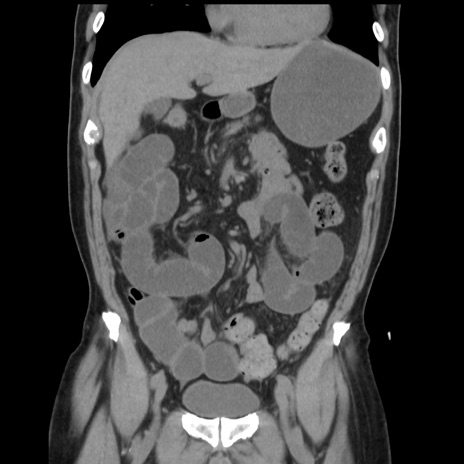

症例16(冠状断像)

【症例】 70歳代男性

【主訴】 腹痛、嘔吐

【現病歴】 約1ヶ月前より間欠的に腹痛と嘔吐あり、当院消化器内科を受診したところCTで多発する肝臓のLDAを指摘され、精査中であった。以降は消化器症状は安定していたが、2日前より嘔気と腹痛があり、同日より排便・排ガスが消失した。改善認めず、 本日、救急外来を受診した。

【既往歴】 大腸ポリープ切除後。

【身体所見】意識清明・会話良好、BT 36.3℃、BP 127/80mmHg、 P 80bpm、腹部:膨満あり、平坦・軟、上腹部正中および下腹部正中に圧痛あり、反跳痛なし、筋性防御なし。

【データ】WBC 7200、CRP 0.77